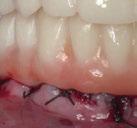

Este último aparato funcional se mantuvo en boca durante 8 meses, tras haber conseguido la mejoría esperada en cuanto al aspecto facial (figura 17) y las relaciones oclusales (figuras 18 a 22). La mordida abierta lateral producida es fácilmente solucionable en la siguiente fase de tratamiento.

(USS), como se aprecia en las figuras 23 a 25, comienza la segunda fase de tratamiento. Esta duró tan solo 12 meses debido a que gran parte de las relaciones oclusales habían mejorado durante la etapa anterior. Los resultados finales del tratamiento se observan en las figuras 26 a 30 , con la corrección de la clase molar y canina, el resalte y la sobremordida, el centrado de las líneas 1/2 y la curva de Spee. La mejoría en la macro, mini y microestética facial se aprecia en las figuras 31 a 33 , a pesar de la evidente desviación del mentón hacia

la derecha debida a la asimetría ósea detectada al inicio del tratamiento. En la figura 34 se muestran los cambios producidos por el tratamiento ortopédico-ortodóncico realizado, con la mejoría de casi todos los valores cefalométricos analizados, así como los ángulos de la convexidad (160 º), nasolabial (100 º) y mentolabial (118 º) más cercanos a la norma.